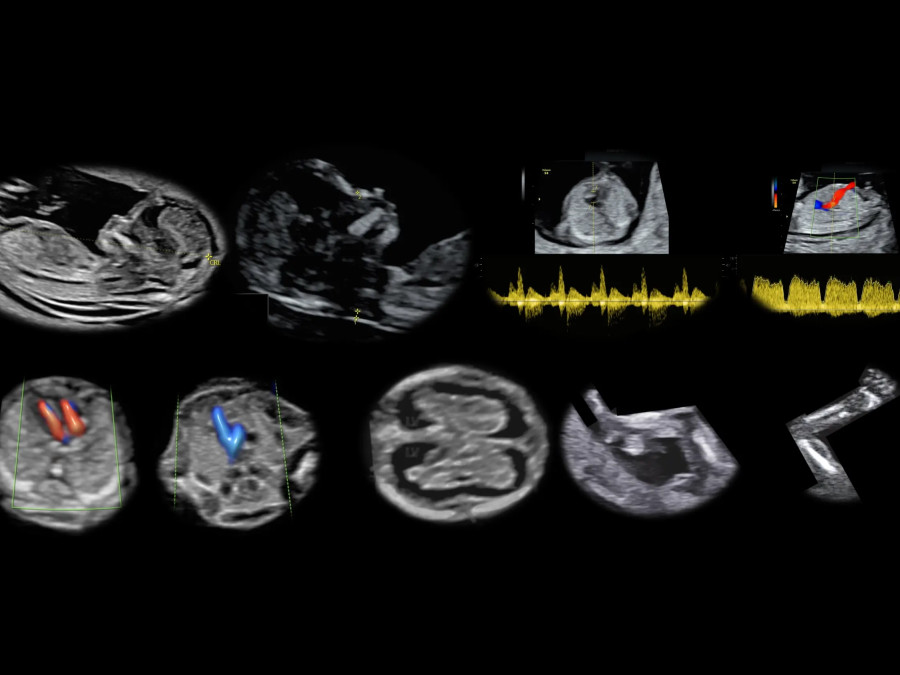

Υπερηχογραφήματα

Υπερηχογράφημα ανατομίας Β’ επιπέδου

Υπερηχογράφημα ανάπτυξης Doppler